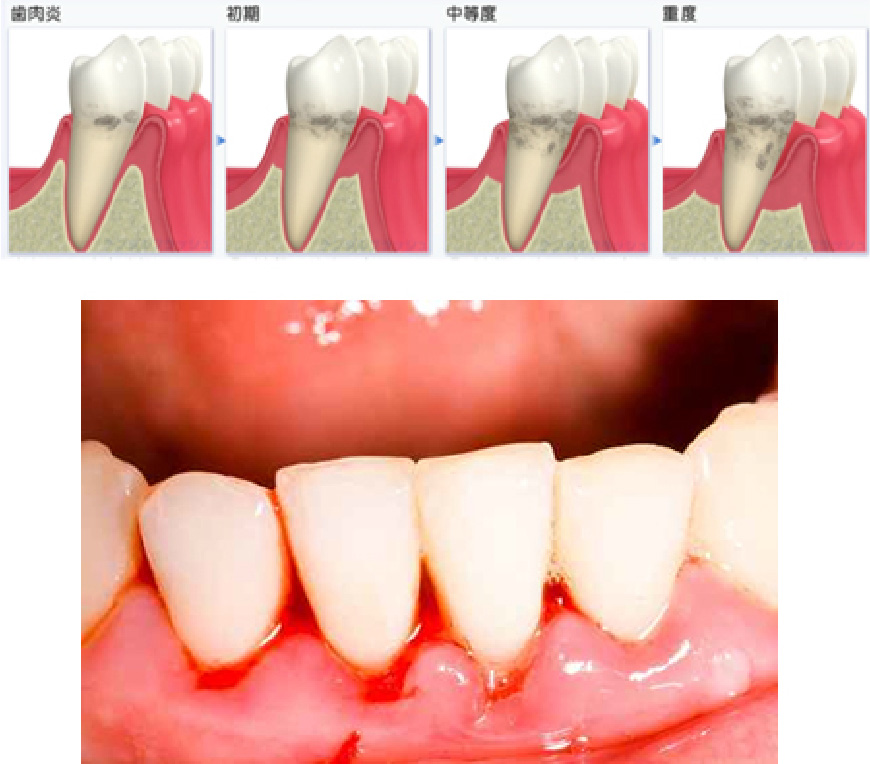

歯周病とは、歯を支えている組織(主に歯槽骨)が破壊され、結果的に歯の喪失を招く疾患です。日本人の抜歯理由第一位は歯周病です。

歯周病は自覚症状がないまま重度に至り、気が付いた頃には手遅れになっていることが少なくありません。一度失った歯槽骨は、現在の医療技術では完全に再生させることは不可能です。

歯周病は、健康なときから予防をスタートすることが肝心です。また、初期~中等度に進行している場合には適切な歯周治療を受け、重度に至らないための予防行動が必要です。